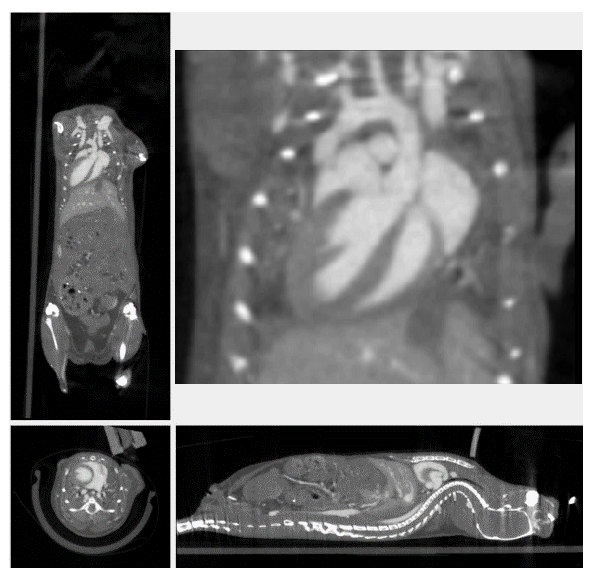

3、心血管研究

隨著造影劑及心跳門控技術(shù)的發(fā)展, micro-CT成為臨床前活體動物心臟研究的有利手段之一。micro-CT可以在相對短時間內(nèi)獲得心腔高分辨率的三維圖像,可以對心臟的形態(tài)學和整體心室收縮指數(shù)進行量化,如心搏量體積、射血分數(shù),心臟輸出量等。收縮功能異常常見于心血管疾病中,尤其在早期臨床表現(xiàn)中,而舒張功能的改善與生存時間的延長有關(guān),因此,使用micro-CT評價舒張和收縮功能的評估是至關(guān)重要的,對心肺疾病的診斷、預(yù)后具有重要意義。

心臟門控成像

通過造影劑進行心臟結(jié)構(gòu)成像和生理機能的監(jiān)測。對心肌肥大,心律不齊和心臟射血分數(shù)進行測定。

心臟門控成像.png